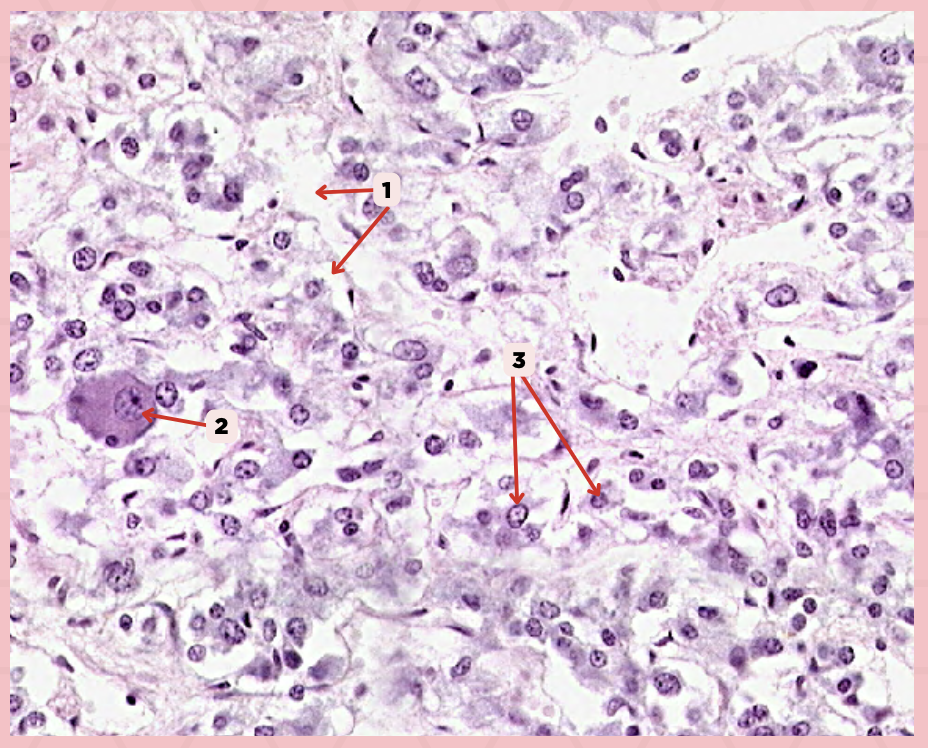

Pancreas

Identify the specimen.

Islets of Langerhans

Identify the structure labeled as 1.

Pancreatic Acini

Identify the structure labeled as 2.

Reticular Tissue

Identify the structure labeled as 3.

Beta-cells

Which cells occupy the central area of #1?

Pancreatic Acini

#3 delineates the pale- staining cells from the darker-staining cells. What do you call the darker-staining cells?